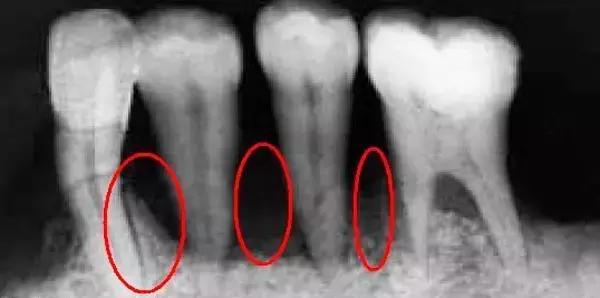

所谓的黑三角,是指牙龈不能完全覆盖两个牙齿的牙颈部与接触点之间的间隙时,那个呈三角形的空洞区域。其实,黑三角最让人恐惧的并非是它不好看甚至“说话漏风”,而在于黑三角无法自我修复,甚至可能越来越严重。由于有了这个额外的空洞,很容易导致食物嵌塞,更是给细菌营造了一个良好的储存环境,对口腔健康大大不利。

牙周炎是导致牙龈萎缩和牙槽骨吸收的“元凶”之一,而这两者都会导致牙根过多暴露在外。当这种情况发生时,黑三角也就出现了。

牙齿拥挤的患者都需要进行牙齿矫正,但是牙齿拥挤本身就会导致牙龈萎缩。严重的牙齿拥挤会导致牙结石的堆积,从而导致长时间的牙龈炎症。牙齿排齐后,相邻间牙齿的间隙也就暴露出来,形成了黑三角。